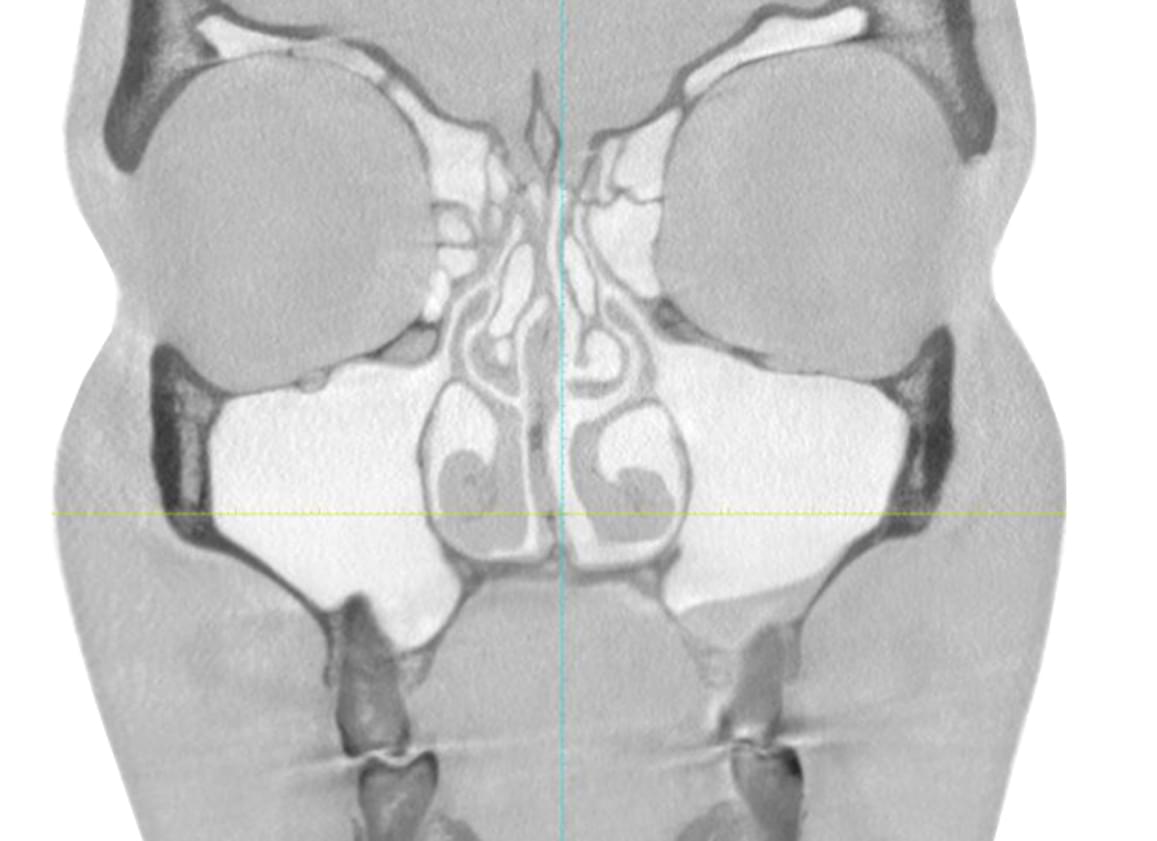

Výpočetní tomografie

(3d čelisťové snímky a snímky ústní dutiny)

CBCT Maxilofaciální diagnostika

Využíváme nejmodernější zařízení